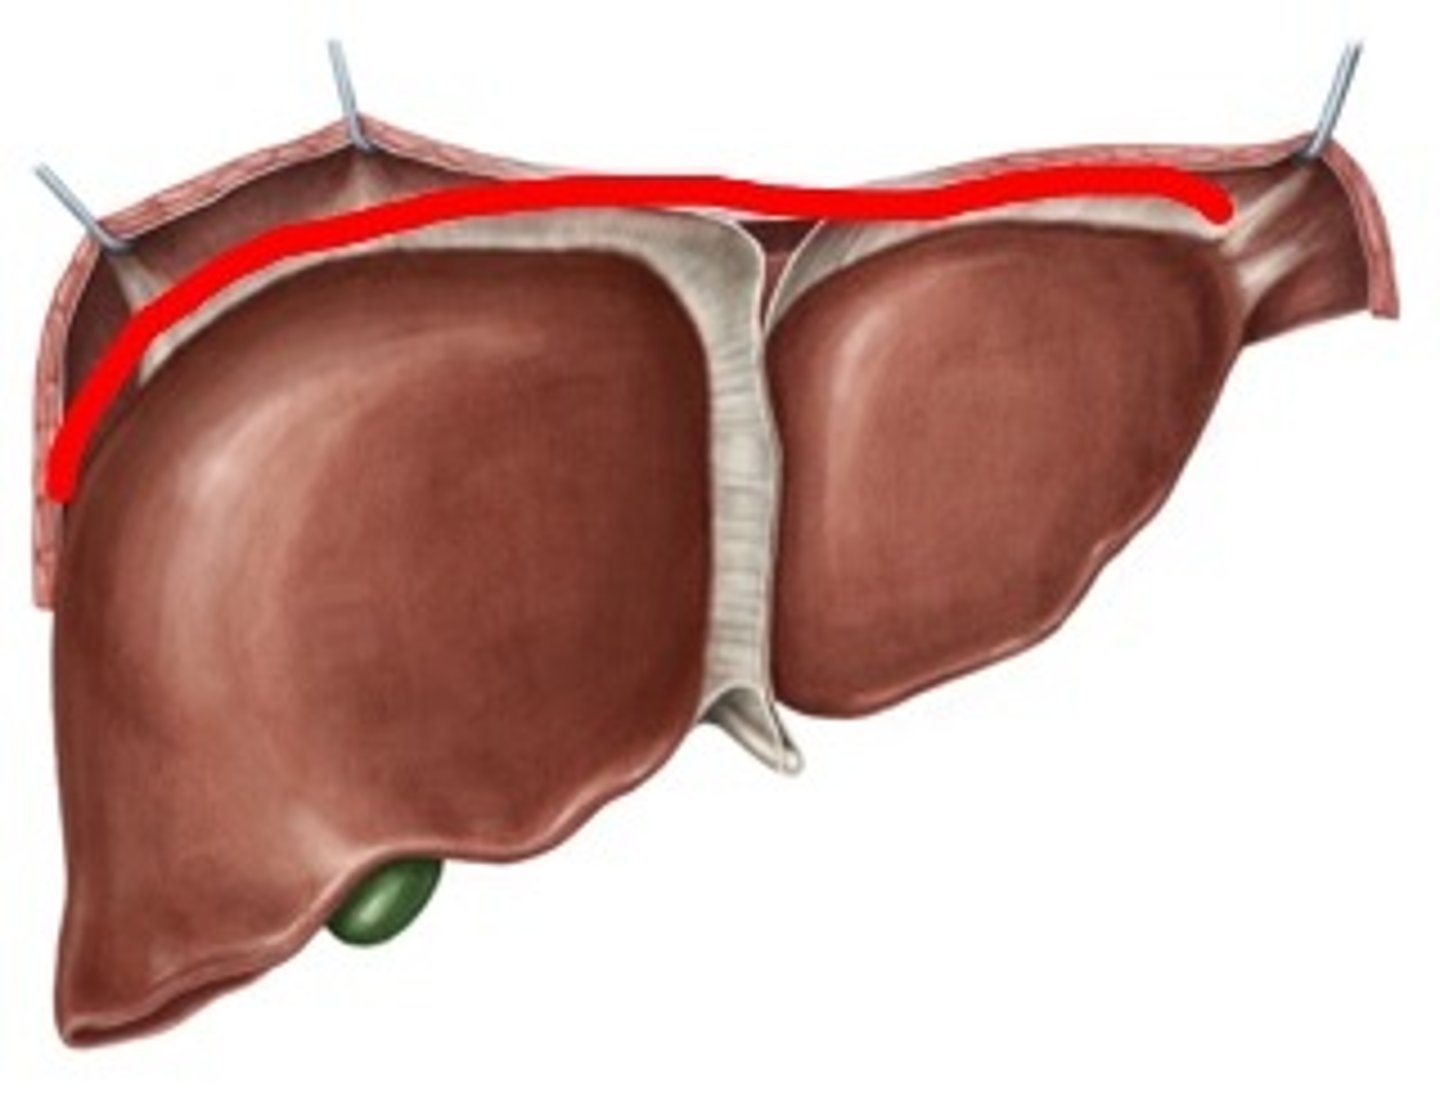

falciform ligament

right lobe (of liver)

left lobe (of liver)